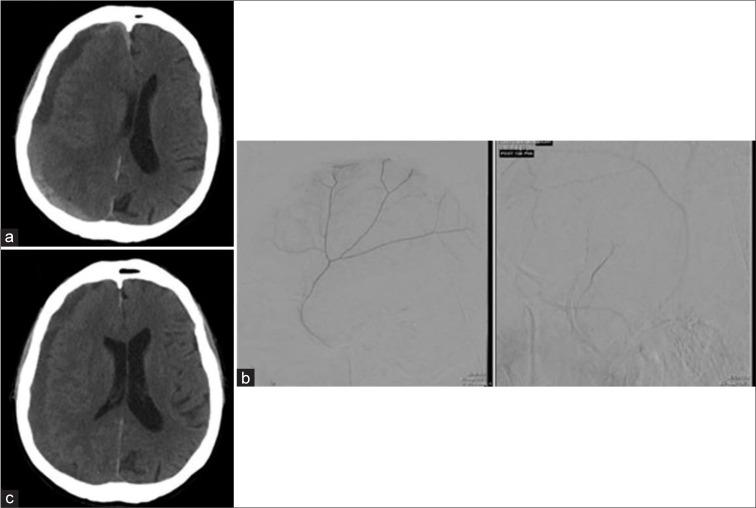

A 74-year-old male with acute myeloid leukemia presented to the emergency department with persistent headache and emesis following fall without head trauma. Computed tomography (CT) revealed a 12 mm right-sided, mixed density SDH. Platelets were <2000/mm initially, which stabilized to 20,000 following platelet transfusions. He then underwent right eMMA without surgical evacuation. He received intermittent platelet transfusions with platelet goal >20,000 and was discharged on hospital day 24 with resolving SDH on CT.

High-risk surgical patients with refractory thrombocytopenia and symptomatic cSDH may be successfully treated with eMMA without surgical evacuation. A platelet goal of 20,000/mm before and following surgical intervention proved beneficial for our patient. Similarly, a literature review of seven cases of cSDH with comorbid thrombocytopenia revealed five patients undergoing surgical evacuation following initial medical management. Three cases reported a platelet goal of 20,000. All seven cases resulted in stable or resolving SDH with platelets >20,000 at discharge.